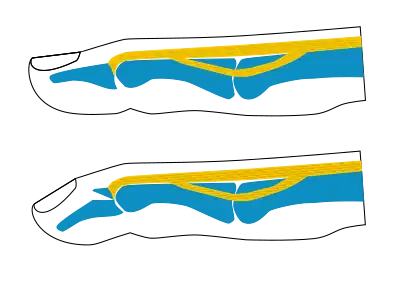

Busch fracture mechanism: because the bit of bone attached to the tendon has broken off, the tendon can't extend the finger tip

Busch fracture mechanism: because the bit of bone attached to the tendon has broken off, the tendon can't extend the finger tip